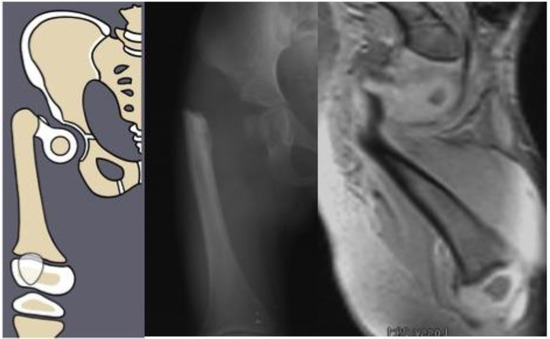

Congenital femoral deficiency (CFD) is a spectrum of deformity, deficiency, and discrepancy of the femur, hip, and pelvis [1]. The most common presentation and most reconstructable types have bony and/or cartilaginous continuity between the femoral head and femoral diaphysis. These are classified using the Paley classification (Figure 1) as Paley type 1a (normal ossification) and type 1b (delayed ossification) (Figure 2) [1,2,3,4,5,6,7,8,9,10,11]. Type 1b cases have severe proximal femoral varus, flexion and retroversion, and acetabular dysplasia, as well as soft tissue flexion, external rotation, and abduction contractures of the hip [1,2,3,4,5,6,7,8,9,10,11].

Figure 2. Paley type 1b2 (neck type) CFD example. Illustration (left), radiograph showing delayed ossification of femoral neck (center), and MRI showing cartilaginous neck (right).